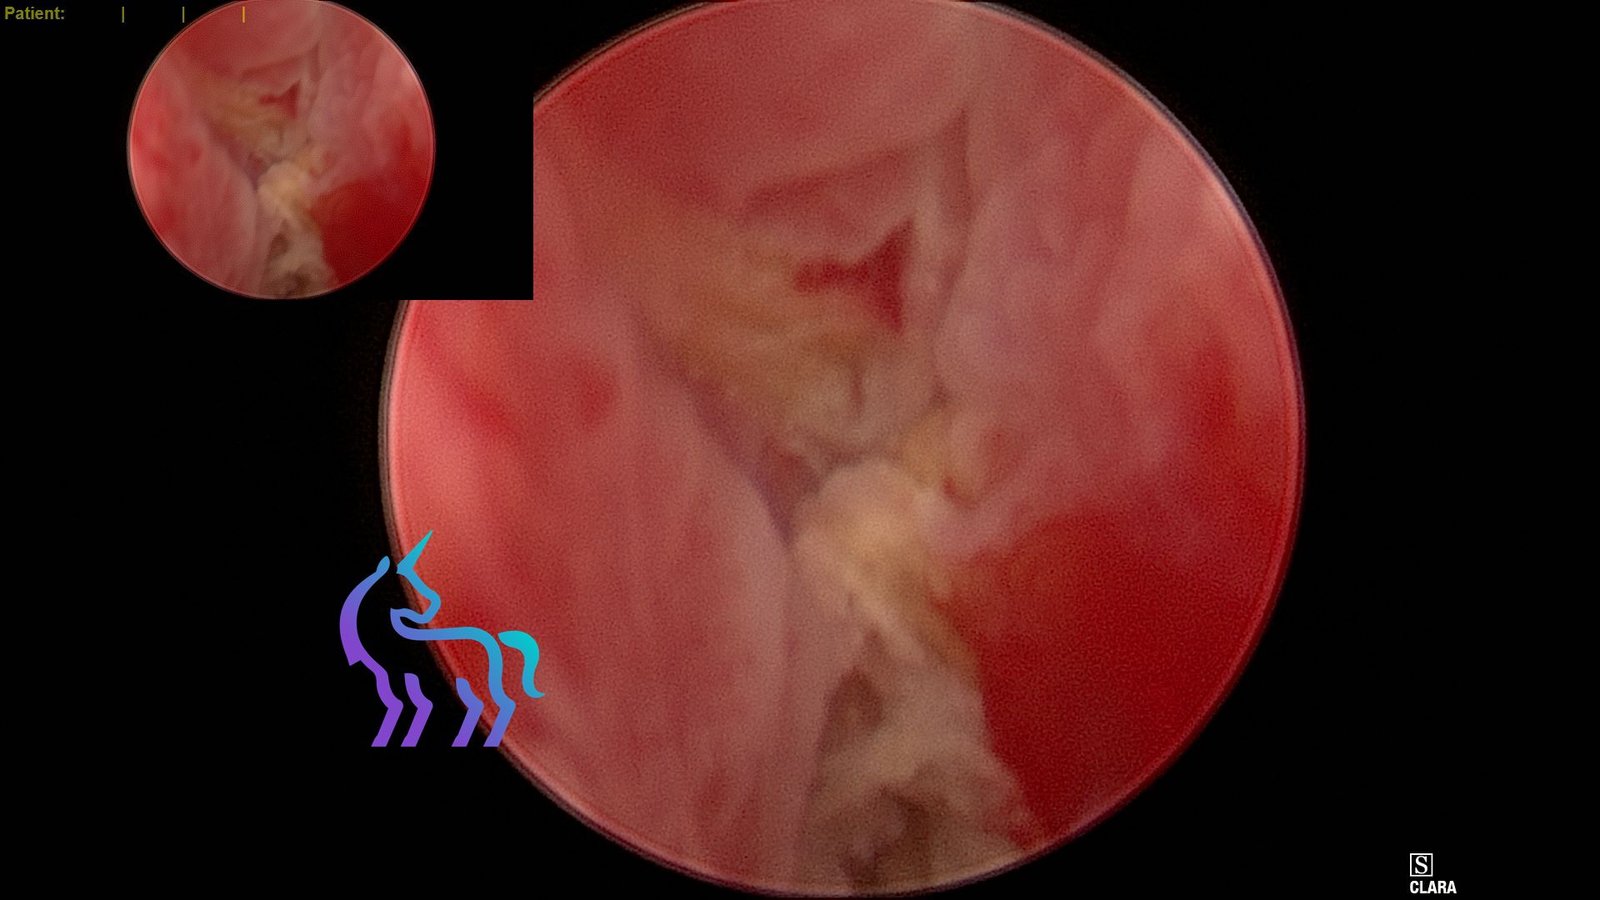

Comme présenté dans la vidéo (collapsus de la trachée), nous utilisons un bronchoscope Karl Storz® couplé à une caméra FULL HD Tricapteur et un écran haute résolution de 27 pouces.